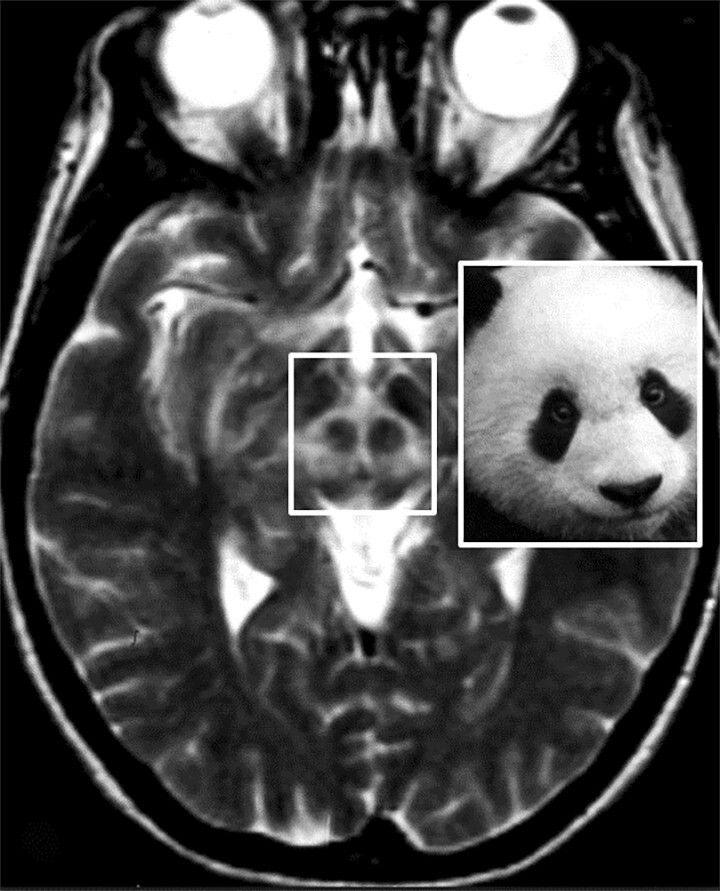

Abb. 69.5 Parkinson-Syndrome: Differenzialdiagnose Morbus Wilson.

Beim Morbus Wilson kommt es zu variabel ausgeprägten Signalveränderungen in den T2w MRT-Sequenzen im Mittelhirn um die Substantia nigra und den Nucleus ruber (Markierung: Giant Panda Sign; Pandabärzeichen).